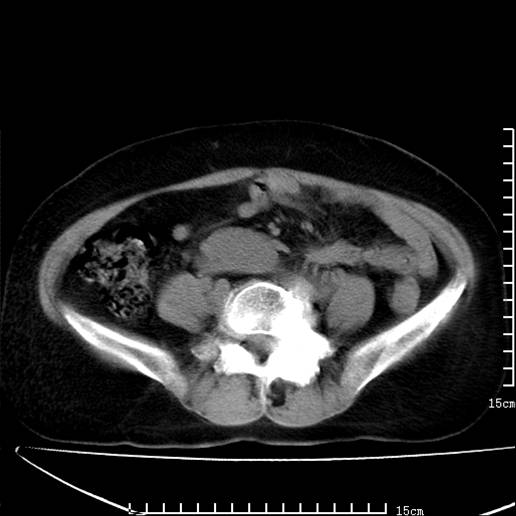

以下是引用pujunzhi在2008-5-30 15:31:00的发言:[br]异位肾—盆腔肾。当看到肾窝无肾脏时,要想到孤立肾和异位肾,异位肾最常见是盆腔肾,偶见胸腔,易误认为肺占位,只要想到就不会漏诊。建议增强扫描。